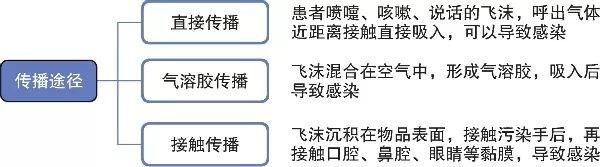

“未知的事物才是最可怕的”,首先,我們要了解新型冠狀病毒的傳播方式,這樣我們才能從源頭斷絕新型冠狀病毒的傳播。根據鐘南山院士帶領的廣州呼吸健康研究院研究團隊發布的新型冠狀病毒肺炎的防范指引顯示,新型冠狀病毒可感染包括人在內的多種動物,具有致病力強,傳染性高等特性。其主要傳播方式包括:空氣飛沫傳播、接觸傳播及可能的糞口傳播。

在日常生活中,人與人之間面對面的交流和肢體上的接觸恐怕是再常見不過的事情,但對于新型冠狀病毒來說,上述情況極有可能實現病毒在人與人之間的傳播,這也是新型冠狀病毒的可怕之處,在不知不覺中實現擴散。

空氣飛沫傳播是新型冠狀病毒的主要傳播方式,日常面對面說話、打噴嚏、咳嗽都可造成飛沫傳播。同時新型冠狀病毒還可通過皮膚、結膜等接觸傳播。除此之外,檢查發現,患者糞便可分離出新型冠狀病毒,故未能排除糞口傳播的可能。因此新型冠狀病毒肺炎患者及病原攜帶者作為主要的傳播者,治愈或隔離該部分人群,是切斷新型冠狀病毒傳播的有效途徑。